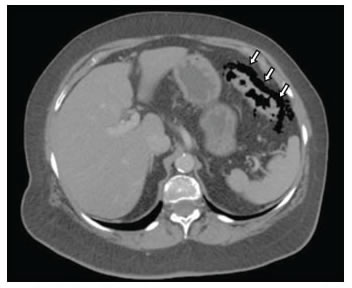

De los 60 pacientes que ingresaron con diagnóstico de diverticulitis, 3 (5 %) presentaron neumoperitoneo sin ningún otro hallazgo radiológico asociado (figura 1). Los tres eran del sexo femenino, con una media de edad de 67 años (rango: 61 a 72), y presentaban dolor abdominal progresivo en el hemiabdomen izquierdo que había aparecido tres a cinco días antes de consultar al servicio de urgencias,

En las tres pacientes, la TC abdominal con contraste mostró el neumoperitoneo pericólico o localizado a menos de 5 cm del asa inflamada sin aire distante (figuras 2 y 3); dos presentaron divertículos en el ángulo esplénico, colon descendente y sigmoide, y una en el colon sigmoide únicamente.